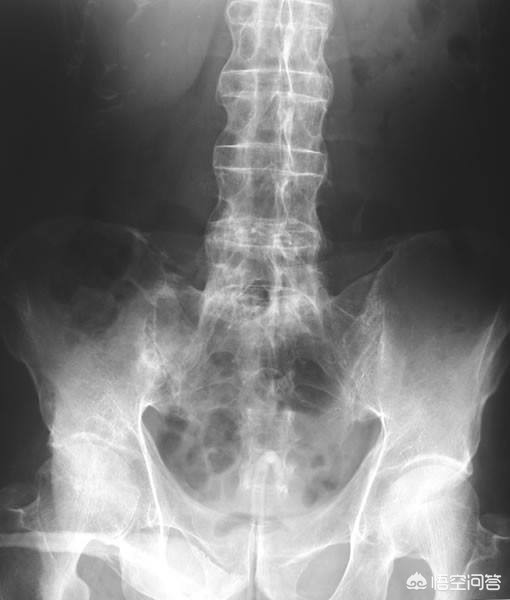

第二,x光检查与ct检查。很多强直性脊柱炎的患者,骶髂关节和脊柱已经发生了明显的炎症性的改变,尤其是有一些患者的腰椎和骶髂关节会出现明显的骨化和软骨的破坏。这种特征性的表现会在x光和ct上有所表现,尤其是当患者病情发展的比较严重、脊柱强直的比较明显的时候会出现一种特殊的x光表现,我们称之为竹节样改变。